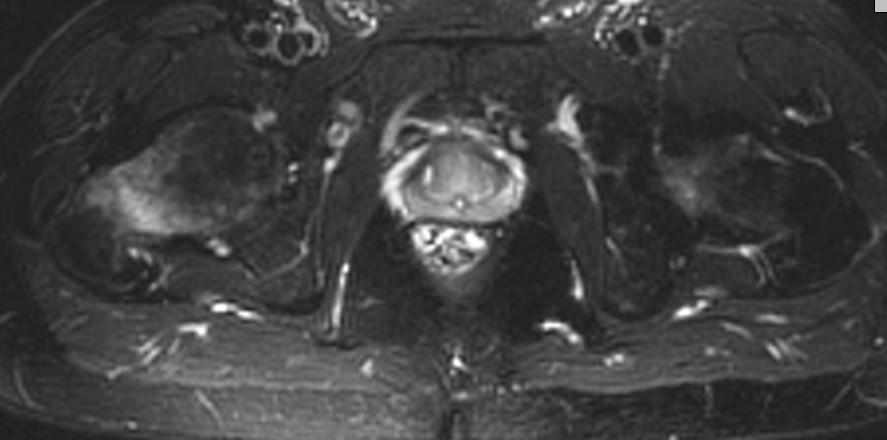

Мужчина 45 лет, социальный, на протяжении двух лет жалуется на хромоту,

умеренную боль в области тазобедренных суставов. Обследован

ревматологом, нейрохирургом,неврологом, вертебрологом (при чем

специалисты - лучшие в городе), есть почти все исследования - КТ, МРТ

организма, анализы на все на свете, диагноза нет, все в пределах нормы.

Попал к нам на консультацию, клинически - жесткий Тренделенбург,

Р-граммы, КТ тазобедренных суставов - все вроде бы ничего (извините,

сейчас нет возможности приложить) По МРТ - такая картинка (приложил),

походку тоже. Что это может быть и как его лечить?